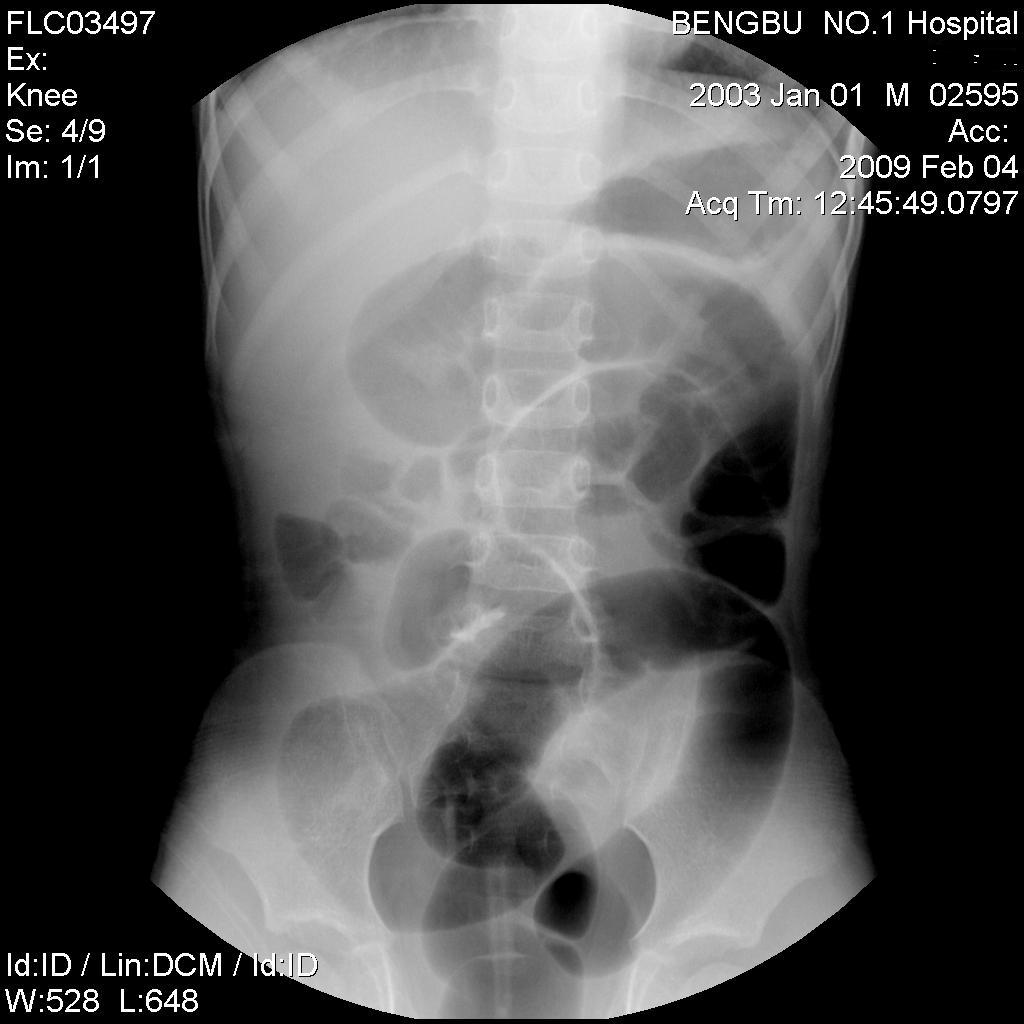

以下是引用杀毒软件在2009-2-5 14:51:00的发言:[br]提示肠梗阻----原因待查----大跨度肠绊---绞窄性可能性小---首选考虑---肠套叠或功能 性肠梗阻可能

以下是引用余辉在2009-2-5 8:52:00的发言:[br]考虑绞窄性肠梗阻,建议行钡剂灌肠检查

以下是引用随光逐影在2009-2-5 1:00:00的发言:[br]考虑肠套叠;建议行钡剂灌肠检查。